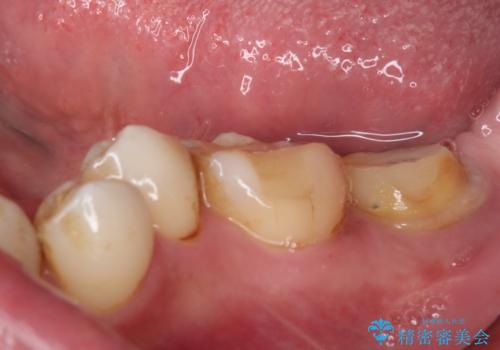

仮歯が途中外れることもなく、無事に補綴治療を行うことができました。

歯石や磨き残しなどが多いため、今後クリーニングを行っていきます。